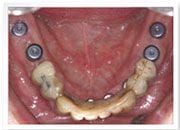

植牙過程

治療前

下顎-植入植體

治療後